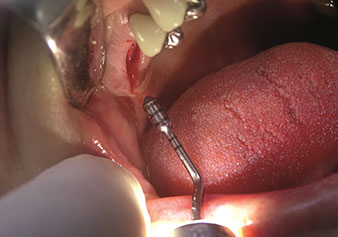

Endikasyon, dahili sinüs lifti

W&H ayrıca iç sinüs lifti için mükemmel bir çözüm sunar. Uygun aletlerle maksiller sinüs hazırlığından sonra

(Şekil 3), yeni uç Z35P (Şekil 4) ile membran hidrodinamik olarak kaldırılır. Aynı uç seti ayrıca Piezo cerrahisi yöntemiyle, artan çaplardaki implant yeri hazırlığı için de kullanılabilir [şekil 3 ve 4, Dr. Mario Kirste’nin (Frankfurt/Oder) onayı ile kullanılmıştır].